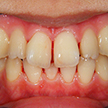

8. 矯正中正面

ジスキングには細心の注意を払い、矯正装置を装着したところです。ちなみに上顎の歯列拡大(少ししか拡大できなかったが)で、下顎左側の2,3番間の叢生が若干ですが改善しています。